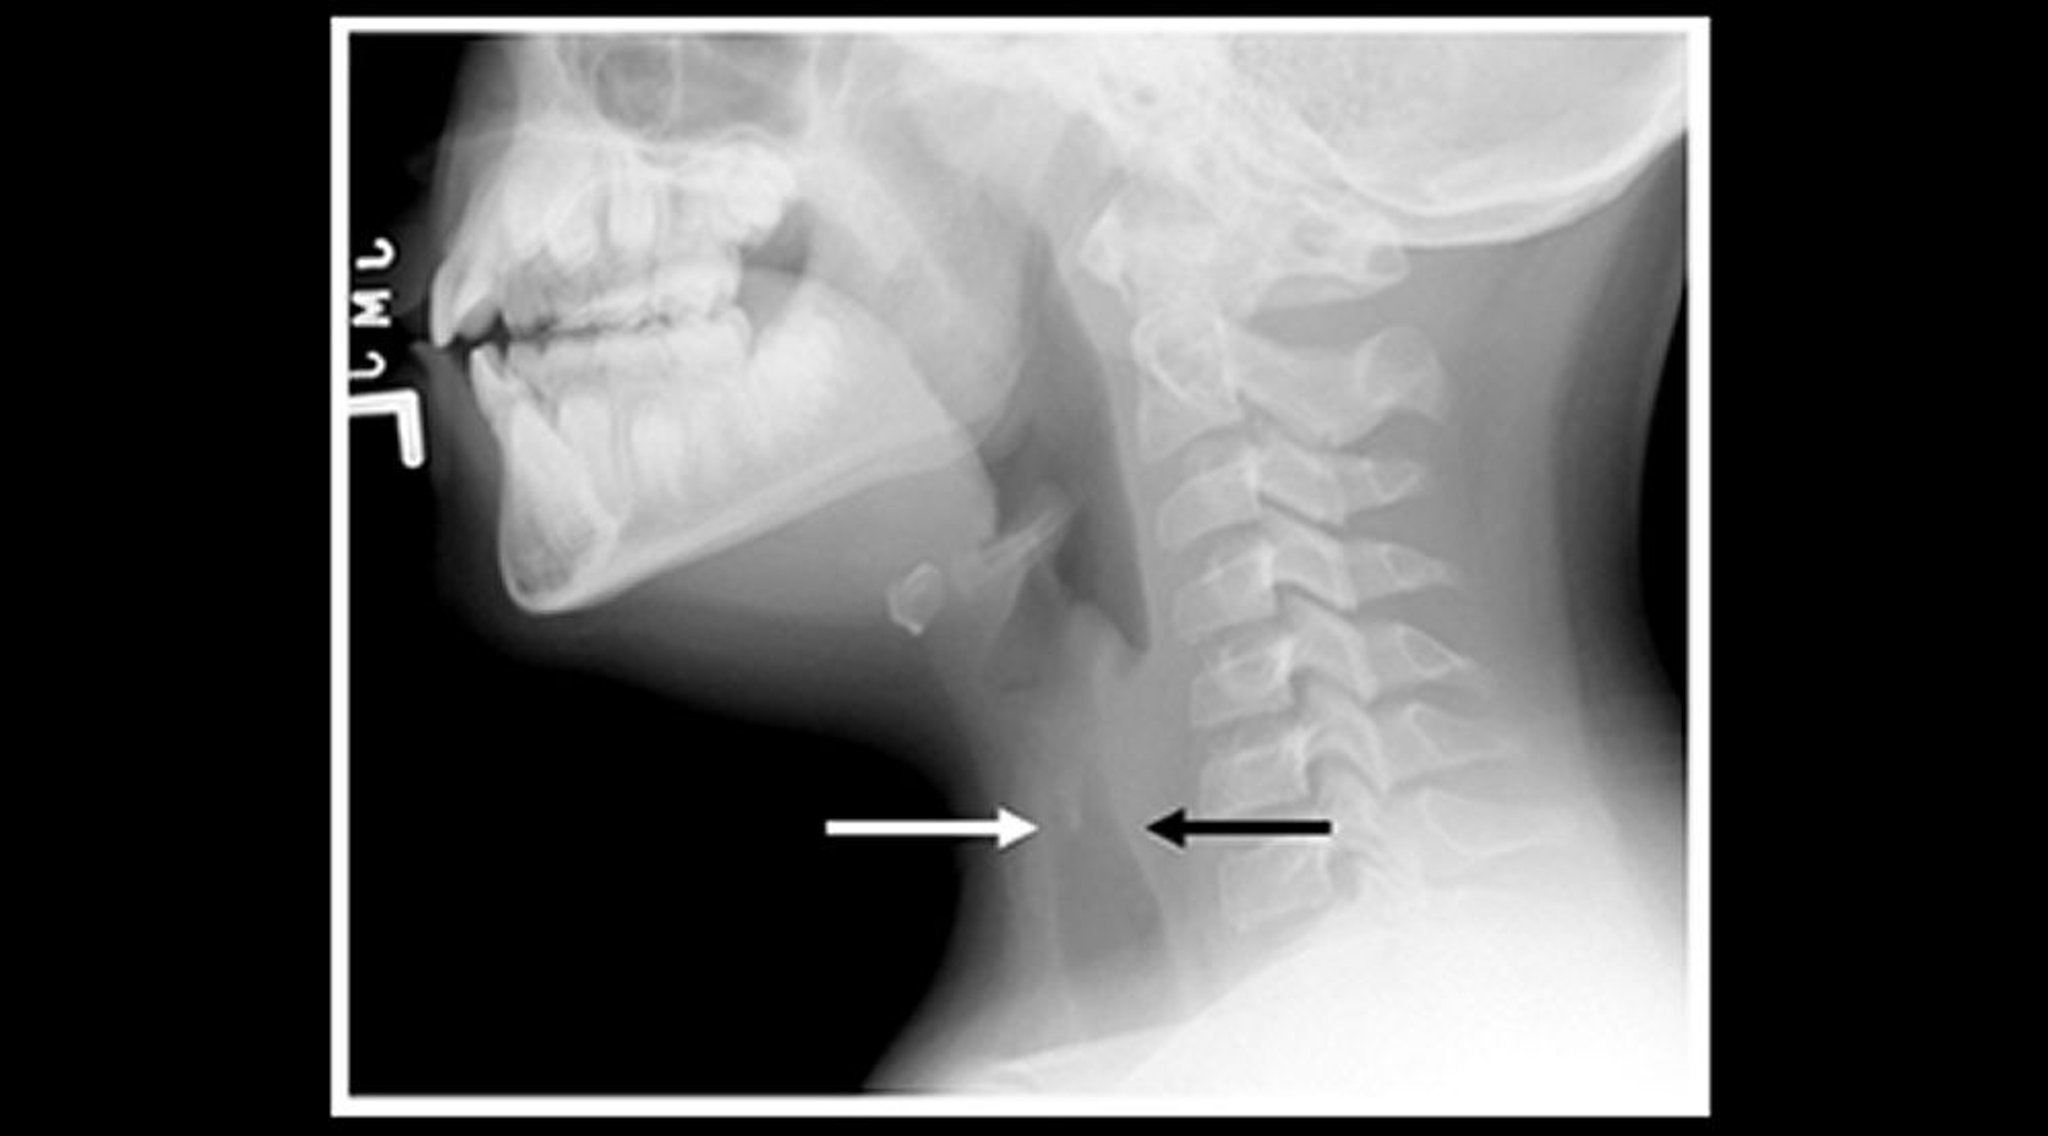

Radiograph of a Child With Croup (Sagittal View)

Soft-tissue neck radiograph of a child with croup shows narrowing of the subglottic tracheal air shadow (arrows) and dilation of the pharyngeal air spaces.

Image courtesy of John McBride, MD.